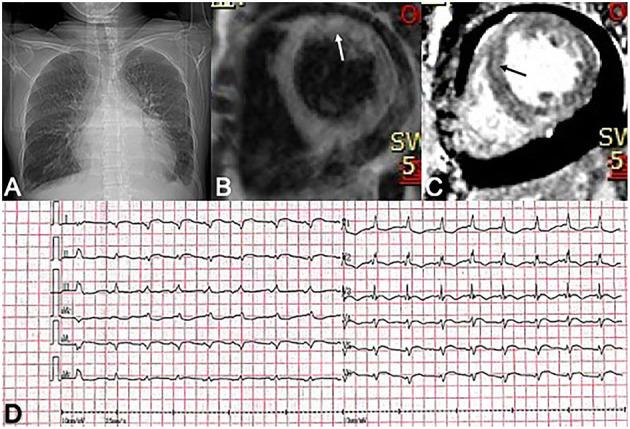

Natural killer/T-cell (NK/T-cell) lymphoma is a rare-type non-Hodgkin lymphoma derived from NK cells or cytotoxic T cells. Here, we present a case of a 40-year-old woman who experienced quick-developed global heart failure and then was diagnosed with NK/T-cell lymphoma through lymphoid biopsy. Neither transthoracic echocardiography nor any radiological images detected a mass in her heart or pericardium. Elevated plasma troponin level and diffused patchy areas of gadolinium late enhancement on cardiac magnetic resonance were compatible with myocarditis. Considering the persistently elevated cytokine level, systemic inflammation symptoms, acute respiratory distress syndrome, and cardiac dysfunction, a cytokine storm secondary to NK/T-cell lymphoma was considered. Due to the refractory malignant arrhythmia, the patient died soon after being admitted to our hospital.

自然杀伤/T细胞(NK/T细胞)淋巴瘤是一种源自NK细胞或细胞毒性T细胞的罕见类型非霍奇金淋巴瘤。在此,我们报告一例40岁女性病例,该患者迅速发展为全心衰,随后通过淋巴活检被诊断为NK/T细胞淋巴瘤。经胸超声心动图及任何影像学检查均未在其心脏或心包发现肿物。血浆肌钙蛋白水平升高以及心脏磁共振钆延迟强化的弥漫性片状区域与心肌炎相符。考虑到细胞因子水平持续升高、全身炎症症状、急性呼吸窘迫综合征及心脏功能障碍,考虑为NK/T细胞淋巴瘤继发的细胞因子风暴。由于难治性恶性心律失常,患者入院后不久死亡。